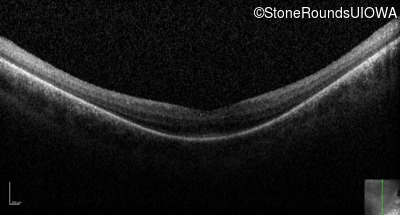

Optical Coherence Tomography - Right - 20/70 -2

Exemplar / OCT Stack

OCT Stack